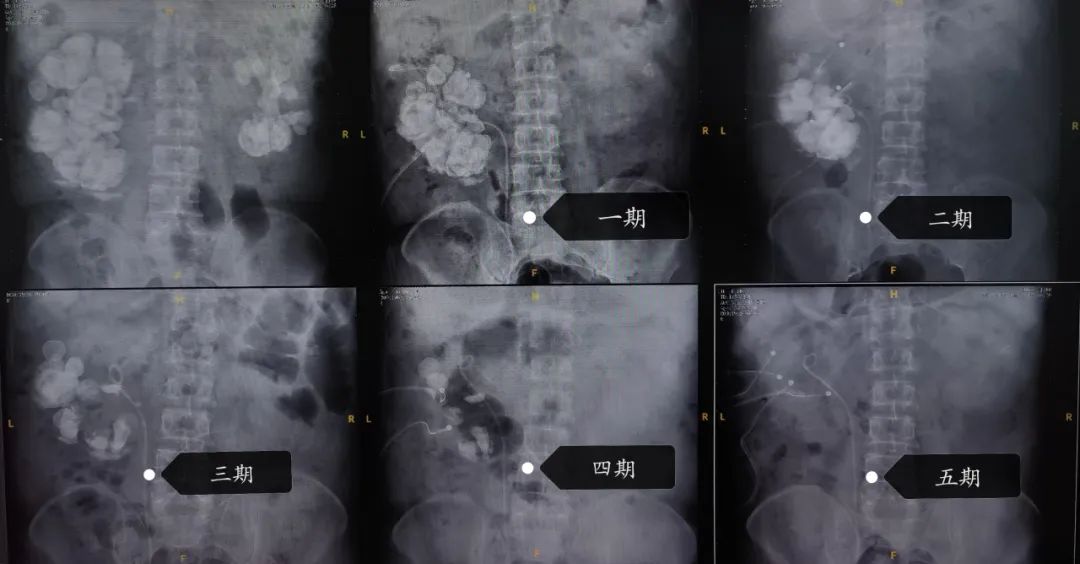

每期术后泌尿系平片对照图

历经半年先后5期手术,最终完整保留住了患者右侧肾脏并清除了右肾的所有结石。术后总肾功能(血肌酐)稳定在150μmol/L(较术前下降90μmol/L),清除结石总重量约1.7斤。

经过详细全面的术前评估与手术规划,刘宇保在排除了手术禁忌后决定为患者实施微创治疗。前期先治疗左肾结石。通过两期微创PCNL将左肾结石清除干净。然后再进一步治疗右侧,计划多期手术,且采用多通道PCNL来完成右肾结石的治疗。